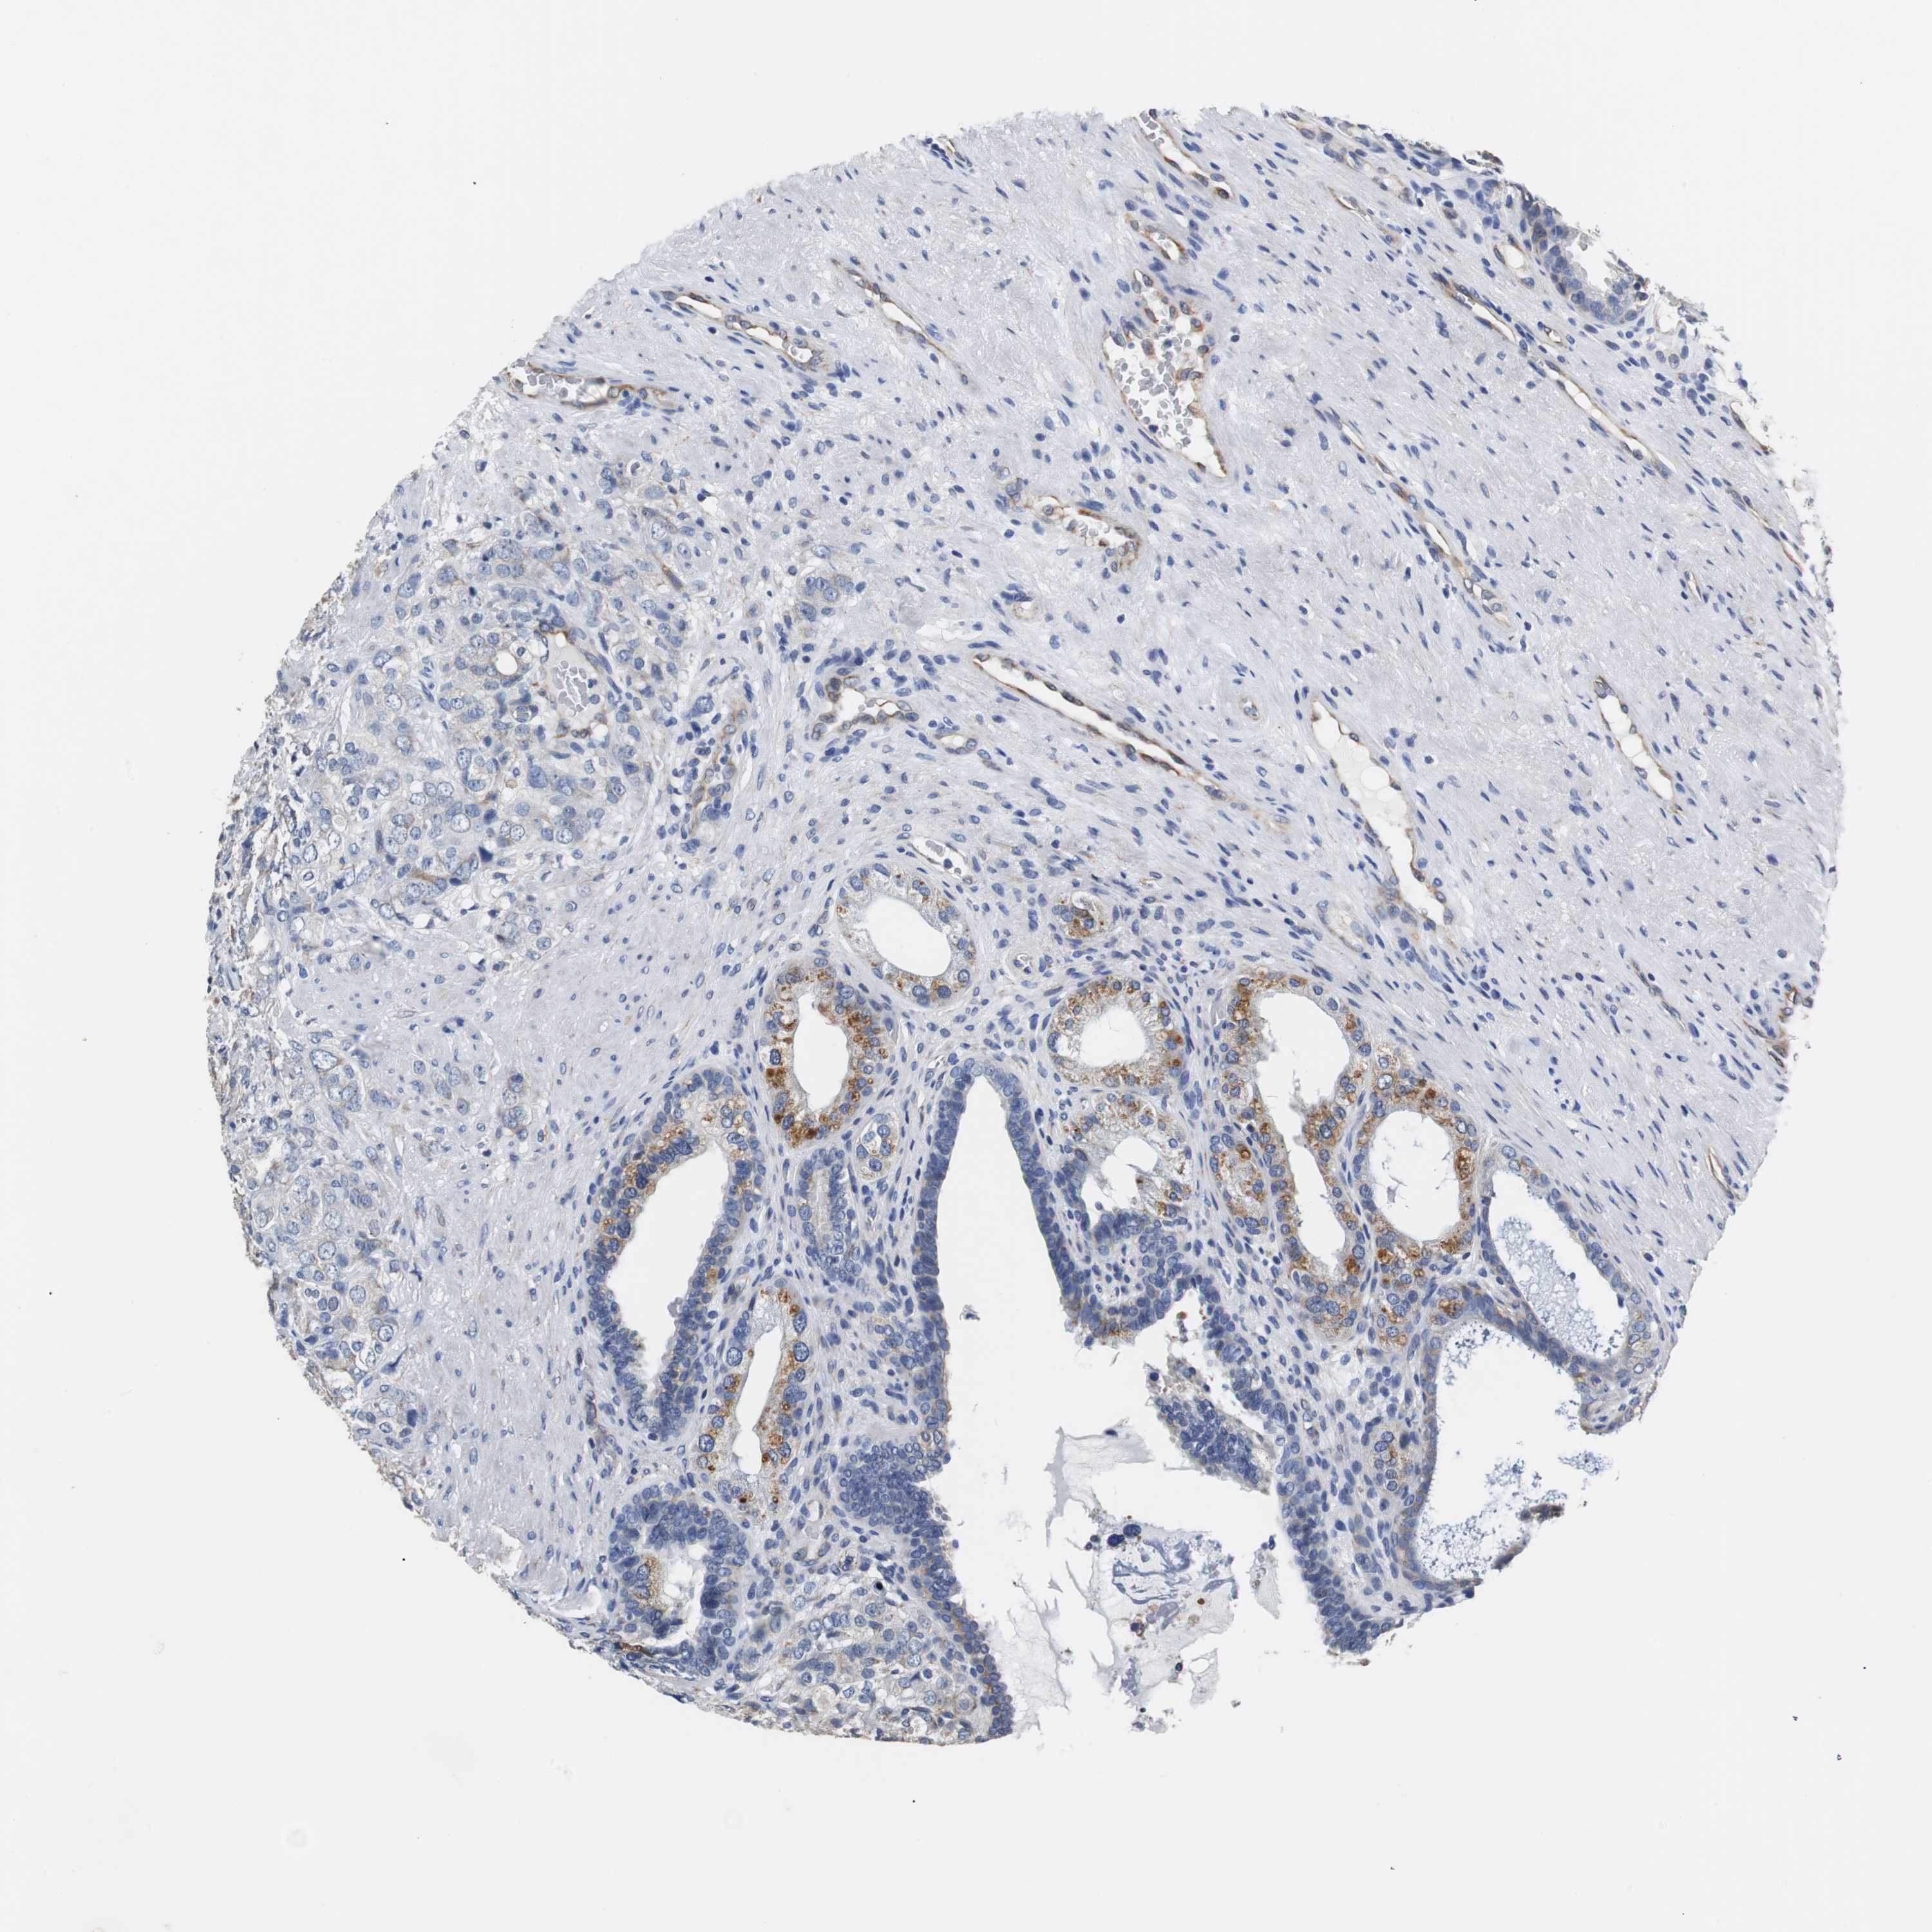

PROSTATE CANCER - Protein expressioni

A mouse-over function shows sample information and annotation data. Click on an image to view it in a full screen mode. Samples can be filtered based on level of antibody staining by selecting one or several of the following categories: high, medium, low and not detected. The assay and annotation is described here.

Antibody stainingi

Antibody staining in the annotated cell types in the current human tissue is reported as not detected, low, medium, or high, based on conventional immunohistochemistry profiling in selected tissues. This score is based on the combination of the staining intensity and fraction of stained cells.

Each image is clickable and will lead to virtual microscopy that enables deeper exploration of all samples and also displays staining intensity scores, fraction scores and subcellular localization as well as patient and tissue information for each sample.

Antibody HPA006277

Antibody HPA006507

Antibody CAB017027

Staining

High

Medium

Low

Not detected

Intensity

Strong

Moderate

Weak

Negative

Quantity

>75%

75%-25%

<25%

None

Location

Nuclear

Cytoplasmic/membranous

Cytoplasmic/membranous,nuclear

Adenocarcinoma, High grade

Adenocarcinoma, Low grade